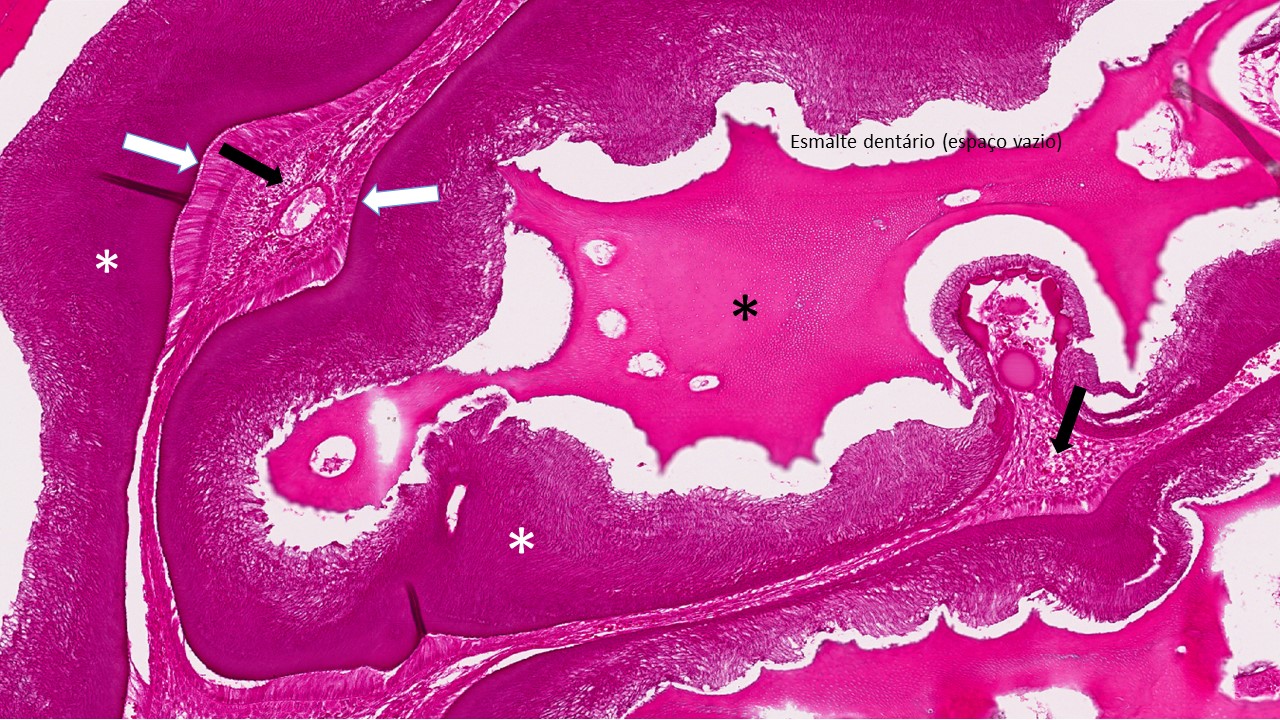

Os odontomas são considerados como anomalias do desenvolvimento (hamartomas). O odontoma complexo consiste em uma deposição desorganizada de tecidos dentários (esmalte, dentina, polpa) que não exibe semelhança anatômica com um dente. No odontoma composto há formação de estruturas que lembram pequenos dentículos com organização do esmalte, dentina e polpa.

Descrição microscópica:

Nota-se grande deposição de tecidos dentários, na maior parte, de dentina com características de dentina tubular madura. Em áreas observa-se fendas ou espaços claros (esmalte maduro que foi removido durante o processo de descalcificação). No interior destes espaços podem ser observadas quantidades pequenas de matriz orgânica de esmalte ou esmalte imaturo. Revestindo essas áreas nota-se células epiteliais odontogências interpretadas como ameloblastos e focos de células epiteliais frouxamente arranjadas lembrando o reticulo estrelado do órgão do esmalte. Tecido conjuntivo lembrando a polpa dentária podem ser identificados mostrando camada de odontoblastos na periferia. Uma delgada camada de cemento com frequência está presente na periferia da lesão.

Dados importantes para diagnóstico:

- Abundância de tecido dentinário (asteriscos pretos);

- Matriz orgânica de esmalte (asteriscos brancos);

- Ameloblastos (setas brancas);

- Células semelhantes à do retículo estrelado (setas pretas);

- Tecido conjuntivo lembrando a polpa dentária com camada odontoblástica (triangulo);

- Espaço do esmalte dentário (perdido na descalcificação)